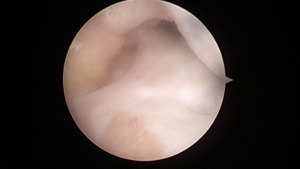

At the time of surgery, diagnostic arthroscopy revealed intact cartilage without any defects or abnormal wear. There was no evidence of a ligamentous injury. The medial meniscus was found to be intact (Figure 4).

The ACL and PCL were intact. The lateral compartment revealed a lateral meniscus tear with the tissue displaced centrally into the notch, impinging on the ACL (Figure 5).